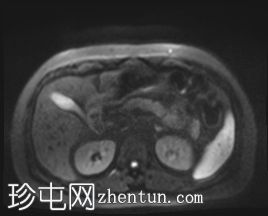

轴位

T2加权像

T1低信号,T2低信号为主的脾脏肿块,内部可见T2高信号分隔,呈进行性强化。肿块中央可见星状瘢痕。

脾脏硬化性血管瘤样结节性转化(SANT),9.8 cm肿块

顾名思义,脾脏硬化性血管瘤样结节性转化(SANT)是一种纤维性血管病变。本病例展示了SANT的一些典型影像学特征,包括边界清晰的病灶,中央可见瘢痕,以及呈放射状进行性强化。这些特征使得术前MRI诊断较为明确。尽管SANT是一种良性病变,但大多数患者仍需行脾切除术以明确病理诊断。